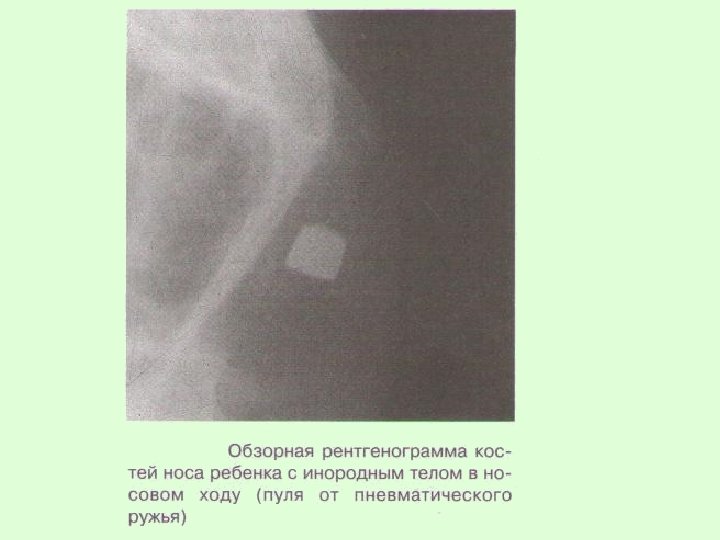

ПЕРЕЛОМЫ КОСТЕЙ НОСА

Жалобы ребенка — на наличие кровотечения из носа, затрудненное дыхание, западение или искривление переносицы.

Клиника. Наблюдаются значительное кровотечение, деформация носа (искривление, западение спинки или скатов), нарушение носового дыхания, гематома окологлазничных участков. При пальцевом исследовании носа можно выявить костную крепитацию его отломков.

Смещение носа возле его основания свидетельствует о переломе лобных отростков верхней челюсти, подкожная крепитация — о переломе решетчатой кости, при котором возникает эмфизема. Для получения данных о локализации и характере перелома носа целесообразно сделать рентгенограмму костей его в прямой и боковой проекциях.